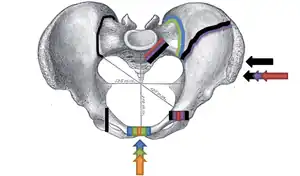

.png)

Pelvic fractures are most commonly described using one of two classification systems. The different forces on the pelvis result in different fractures. Sometimes they are determined based on stability or instability.[9]

Young-Burgess classification

The Young-Burgess classification system is based on mechanism of injury: anteroposterior compression type I, II and III, lateral compression types I, II and III, and vertical shear,[6] or a combination of forces.

Open book fracture

One specific kind of pelvic fracture is known as an 'open book' fracture. This is often the result of a heavy impact to the groin (pubis), a common motorcycling accident injury. In this kind of injury, the left and right halves of the pelvis are separated at front and rear, the front opening more than the rear, i.e. like an open book that falls to the ground and splits in the middle. Depending on the severity, this may require surgical reconstruction before rehabilitation.[12] Forces from an anterior or posterior direction, like head-on car accidents, usually cause external rotation of the hemipelvis, an “open-book” injury. Open fractures have an increased risk of infection and hemorrhaging from vessel injury, leading to higher mortality.[13]